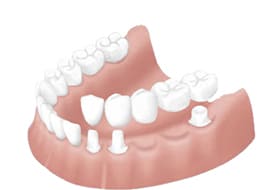

他の治療との比較

歯を失った場合に機能や見た目を回復する為の方法としてブリッジ、入れ歯、インプラントの3つの治療の選択肢があります。

これらの治療法には利点もあれば欠点もあります。ここではこれら3つの治療法について比較紹介します。